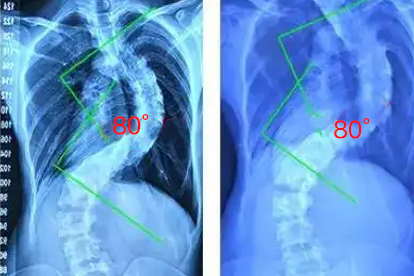

对于Cobb角超过40度的进展性侧弯,可采用后路椎弓根螺钉固定术。严重胸椎畸形需行胸廓成形术联合脊柱矫形。术后需佩戴硬质支具3个月,逐步进行康复训练恢复脊柱活动度。手术存在神经损伤、内固定失败等风险。